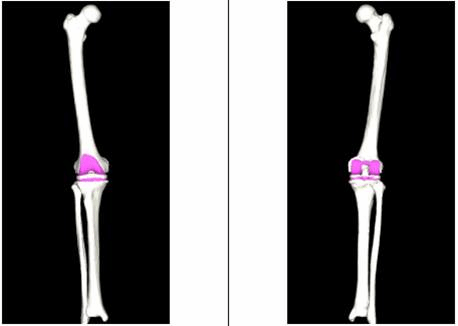

(图二)模拟截骨后假体安放

(图三)IPSI:智能患者个性化导板

(图四)带位点标记的患者膝关节3D模型